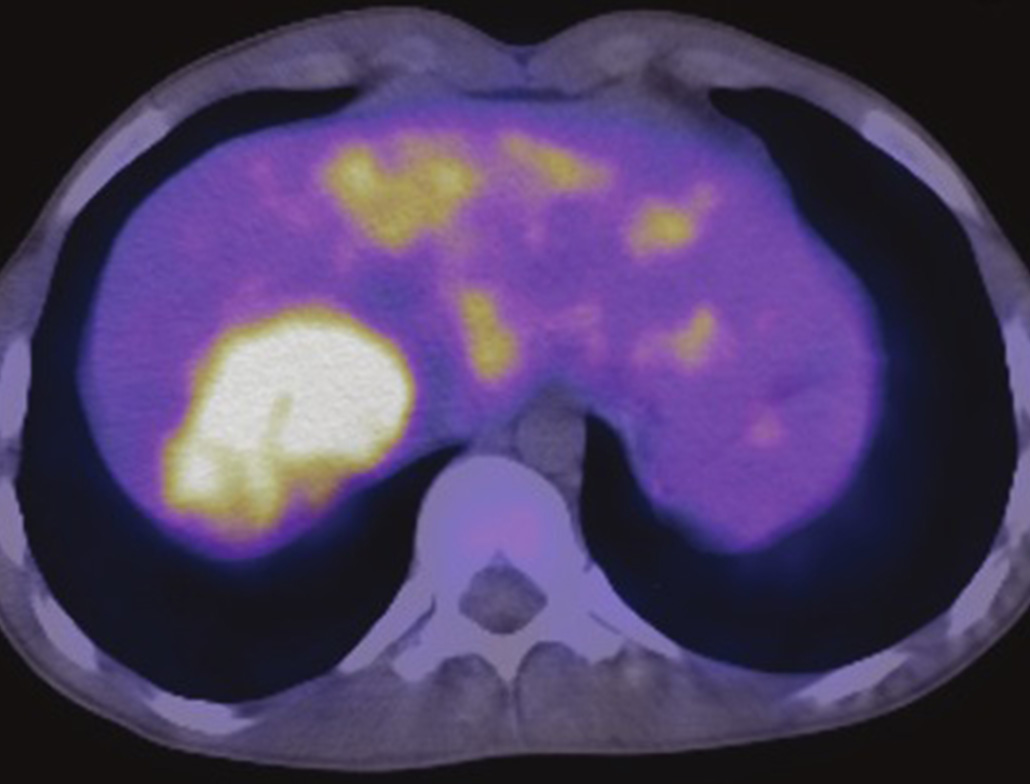

01. 18F‑FDG

Maps glucose metabolism to help find and monitor cancers; also used in heart viability and certain brain conditions for functional assessment.